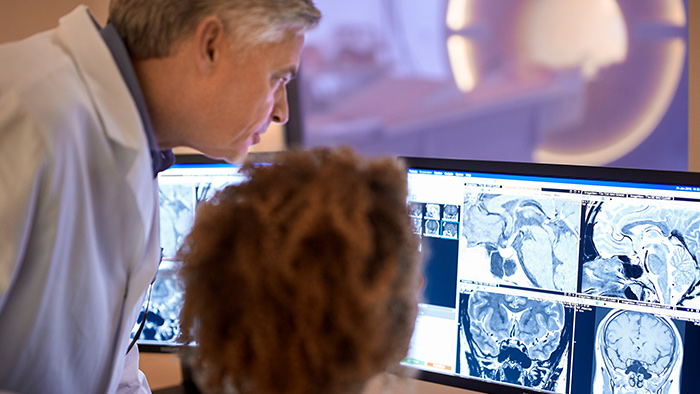

According to Dr. Gellée, the hospital conducts an average of four studies each hour, totaling about 40-45 patients per day on their MR 5300. Studies are read by approximately 50 radiologists in the Bordeaux area. Dr. Gellée is especially satisfied with the image quality of the MR system. "I obtain higher image contrast and more anatomical precision than I was used to,” she says. “When I am able to choose, I request that studies be done on this system, because I get better anatomical image quality. For example, in the knees, I can get great images of the meniscus. To me, it looks as pretty as 3T.”

She values the consistent, reproducible results for all anatomies. “I have seen no bad exam on this system. I always can answer the question asked,” she says.

Also remarkable is the high-quality black blood imaging for vascular and brain imaging as well as the fast stroke imaging. “In stroke imaging we achieve high quality diffusion, T2* with excellent homogeneity and high resolution TOF (time-of-flight) images. Even with this high resolution, the protocol is very fast, which allows us to include emergency imaging in our daily schedule,” she says. “We often can accommodate an emergency patient without disrupting the schedule of other patient’s appointments. Having the MR 5300 helps us in good emergency management in daily practice.”

Also remarkable is the high-quality black blood imaging for vascular and brain imaging as well as the fast stroke imaging. “In stroke imaging we achieve high quality diffusion, T2* with excellent homogeneity and high resolution TOF (time-of-flight) images. Even with this high resolution, the protocol is very fast, which allows us to include emergency imaging in our daily schedule,” she says. “We often can accommodate an emergency patient without disrupting the schedule of other patient’s appointments. Having the MR 5300 helps us in good emergency management in daily practice.”

Imaging speed benefits diagnostic confidence

The MR 5300 with Compressed SENSE is up to 50%** faster for many exams. It can provide routine exams in less than 5 minutes and whole-body exams in less than 20 minutes. Saint-Augustin has taken advantage of that speed to create highly efficient protocols. The hospital’s standard stroke protocol is just about 8 minutes, and standard ENT, prostate PIRADS staging, and endometriosis studies all clock in at just about 10 minutes.***

“We have more speed in 3D sequences,” Dr. Gellée states. “With Compressed SENSE, we can replace two or three 2D scans withone high-quality 3D scan. High quality additional orientations are then obtained by post-processing of the 3D data set, thus saving scanning time.”

Dr. Gellée often takes advantage of the system’s speed to add more sequences to an exam. “When Compressed SENSE reduces typical exam duration, I can add sequences to increase my confidence in diagnosing. For example, post-gadolinium liver scans used to be axial, but now we can use a faster coronal scan. And because I know that the quality will be good the first time, I know I won’t have to repeat the sequence. That frees up time to comfortably add one more sequence,” she says.